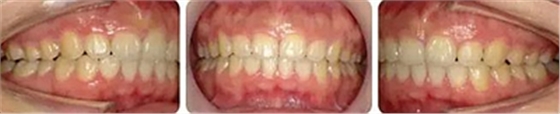

治療23個(gè)月結(jié)束。可見兩側(cè)尖磨牙達(dá)到中性關(guān)系,上下牙列排齊整平,前牙覆合覆蓋正常,中線齊。

結(jié)束3個(gè)月后復(fù)查,無明顯復(fù)發(fā)。

術(shù)后面型

正面觀反笑線糾正,閉口時(shí)唇肌自然。前突側(cè)面型得到改善。

術(shù)前術(shù)后側(cè)貌對(duì)比。